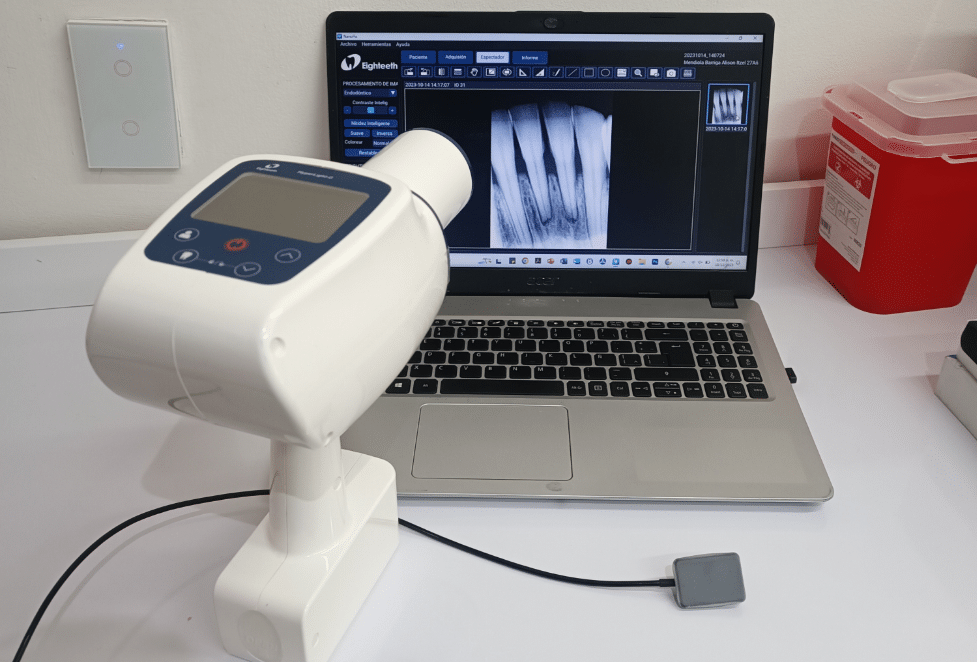

Tecnología, planeación y criterio clinico trabajando para ti.

- 1 Radiografía dental.

- Radiografías dentales*

- Radiografías dentales*